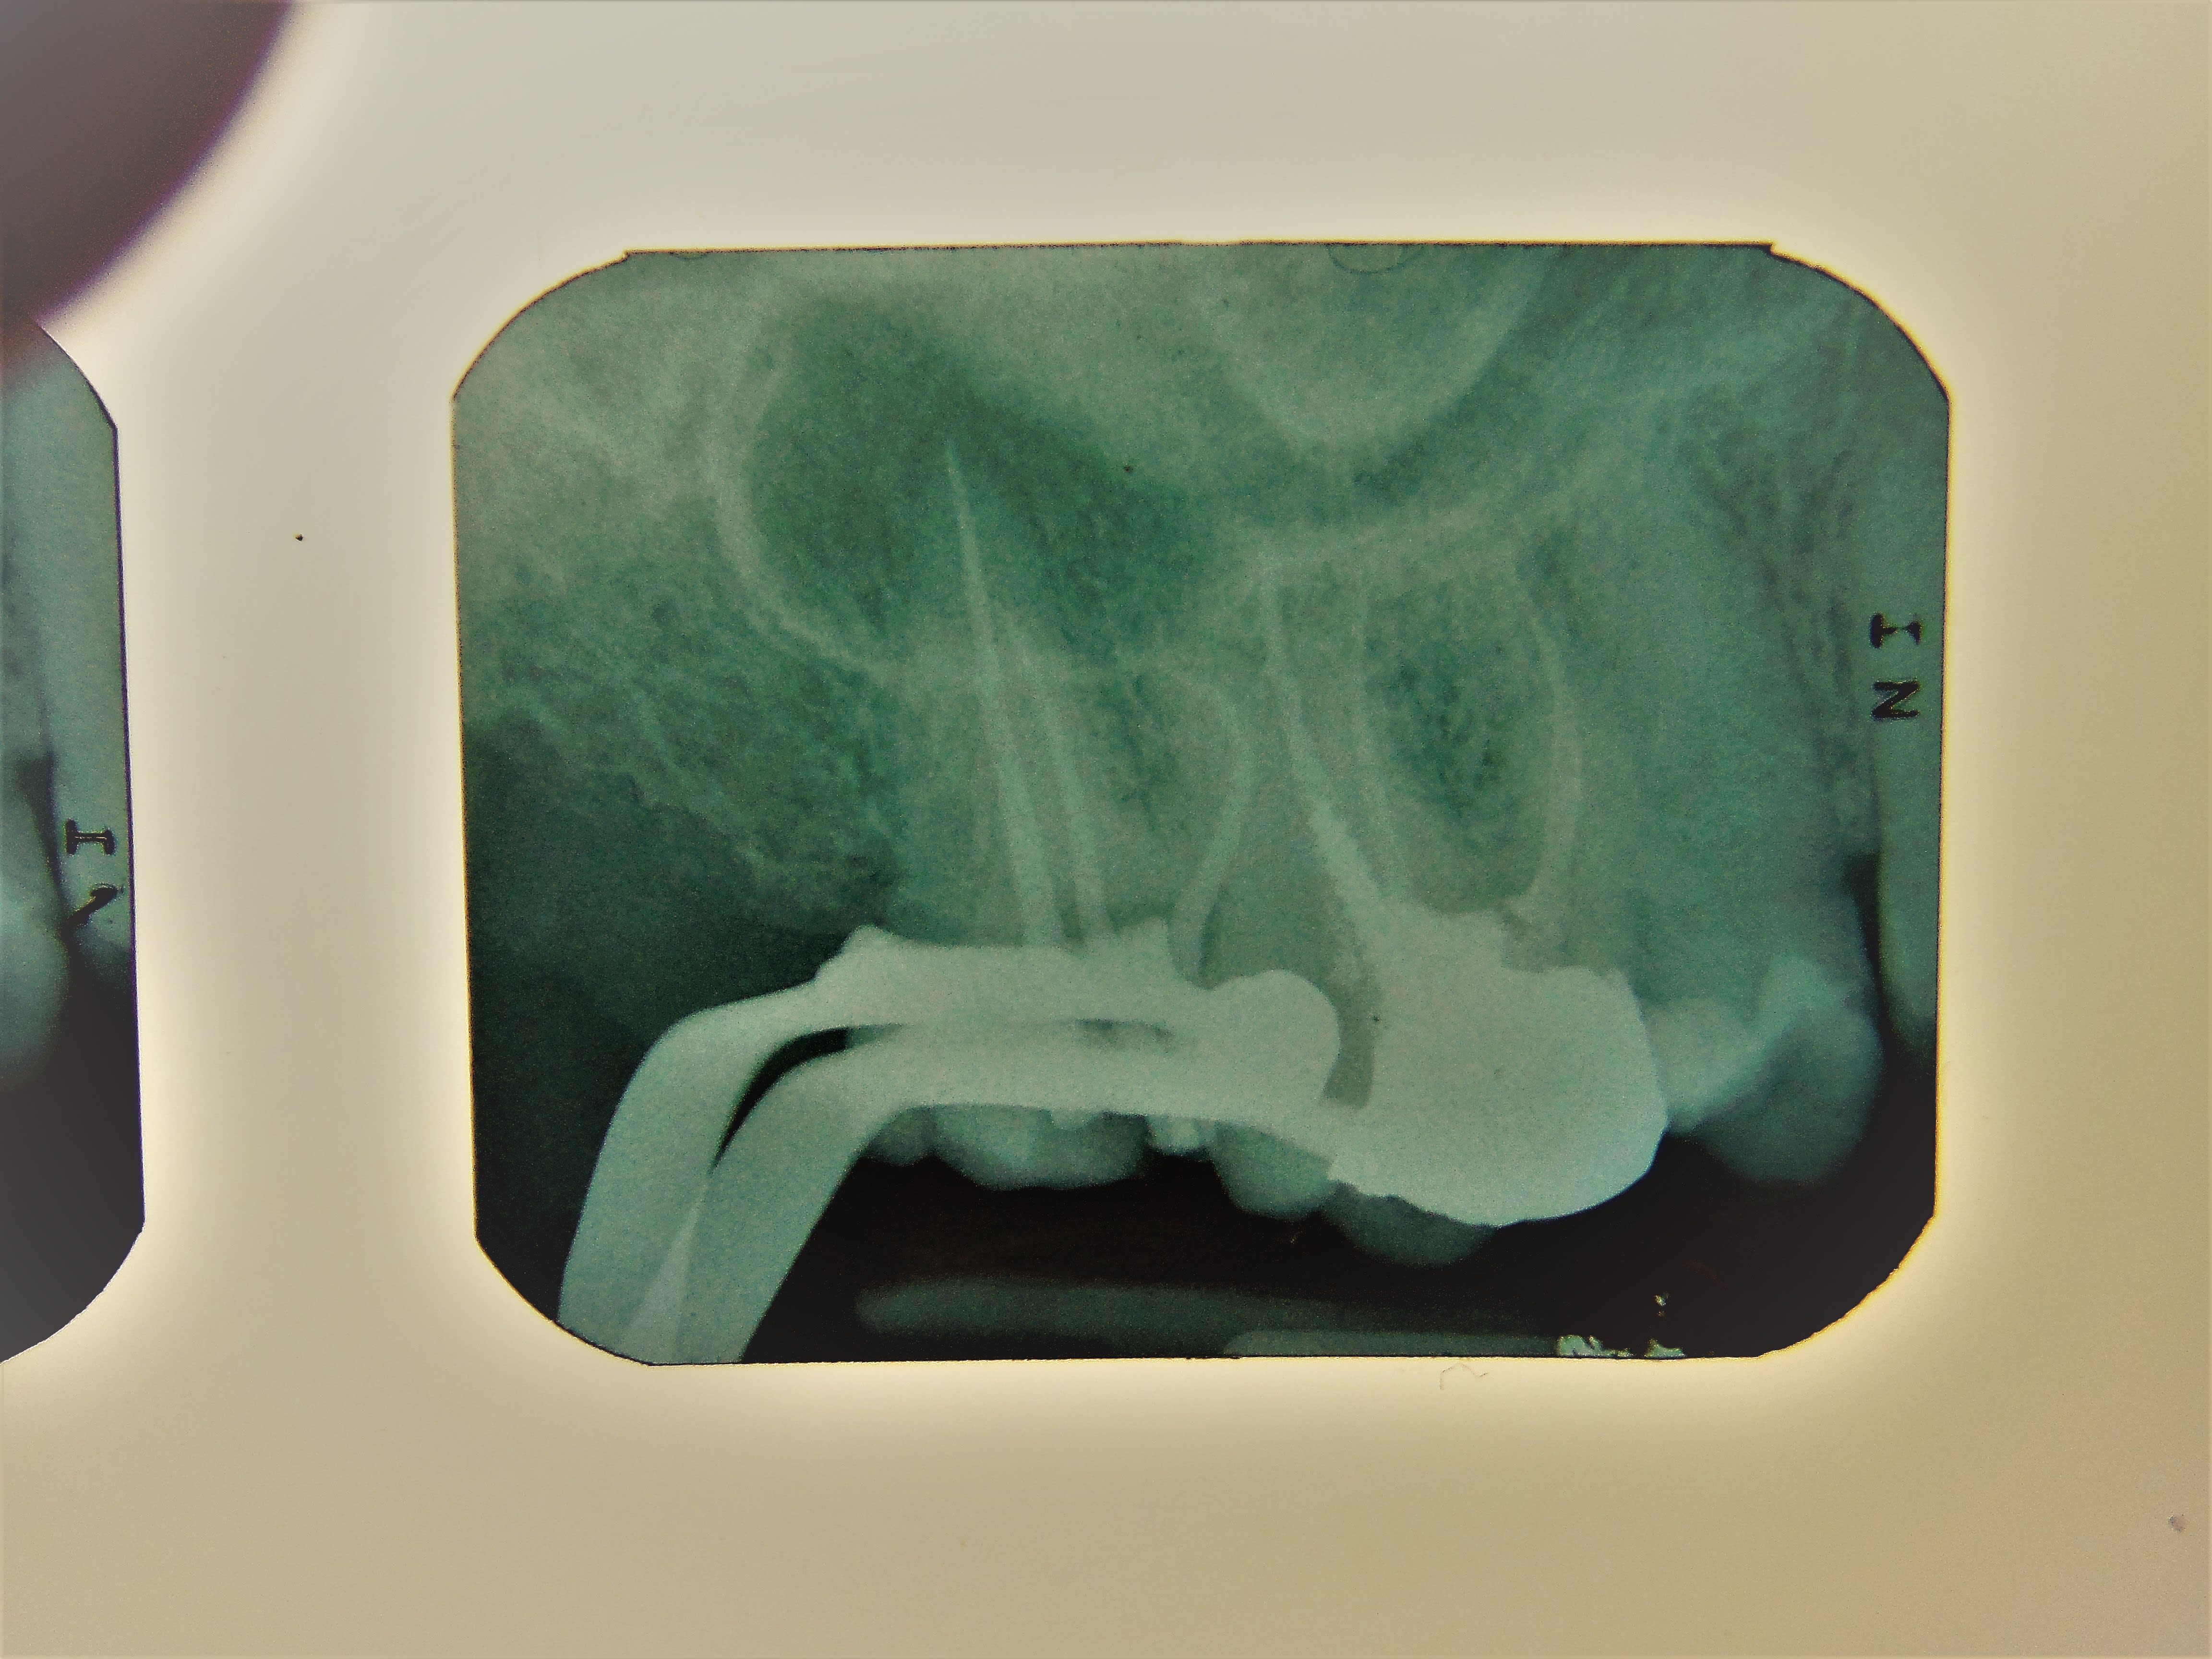

je pense pas qu'il y ait que la double courbure.

J'ai ressorti un cas, à l'époque j'étais en argentique, d'où l’image... de toute évidence j'ai butée dans le crampon et j'avais une double courbure, ça n'a pas cassé. Protapers unervesals.

Ben là il était droit ton crampon, sur ta radio.

Après, la double courbure, c'est le grand classique, mais peut-être qu'avec un instrument plus souple, ou plus solide, ou plus neuf, ou, ou, ou... ça passait. Des fois, il faut un peu de malchance en plus. M'enfin ça, sauf à verser dans le mysticisme, c'est dur de jouer dessus.